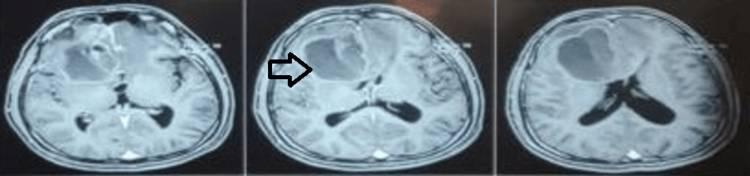

常规术前血液检查在正常范围内,胸部X光检查未发现任何明显异常。大脑的磁共振成像(MRI)发现右额叶存在轴内占位性病变,对左侧胼胝体产生压迫,伴大脑镰下疝。在T1加权图像上,病变表现为等强度(图1),在T2加权图像上表现为高强度(图2),并显示均匀的扩散限制。

图1 术前MRI脑(T1图像);右额叶轴内等强度占位性病变

图2 术前MRI脑(T2图像);右额叶轴内高强度占位性病变